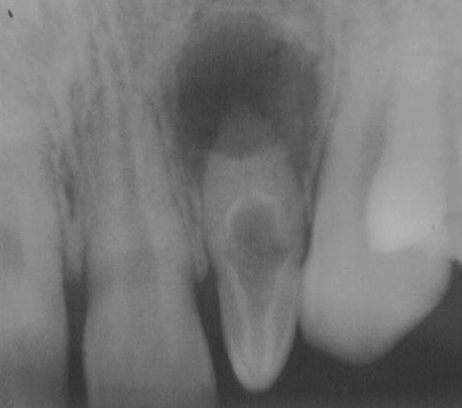

When creating your access in maxillary central incisors, what should you observe in your radiograph?

Anatomy, shape, and location of canal

The access outline is determined by the “incisal limit.” What does this mean?

The use of the incisal edge as the coronal reference point for measuring working length and initiating access cavities, particularly for mandibular incisors

Your access outline should be triangular in shape and 3mm×2mm in size. Why do you need to make an outline?

To have a strategically designed cavity prep designed to provide straight-line access to root canals